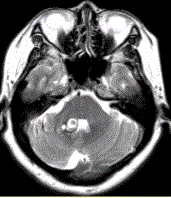

问题 患者女,41岁。头痛半年,加重10d。头部MRI显示如下图。 为进一步确定诊断,下一步的影像学检查是

选项 A.MRI增强 B.FLAIR C.DWI D.MRA E.MRV F.DSA

答案 AE

解析 AE